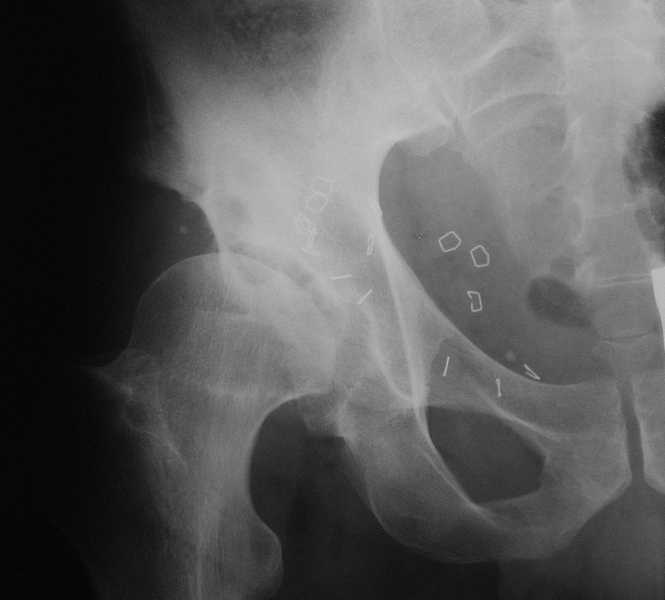

Пациент 40 лет страдает болями в правом тазобедренном суставе более года, хромота, ночные

боли.2 года назад была выполнена лапароскопическая герниопластика косой паховой грыжи.На

снимках на фоне двухсторонних диспластичных тазобедренных суставов кистозные

полости-фиброзная дисплазия? Возникает тактическая задача- пациент нуждается в

экскохлеации образования и пластике или же в одномоментном ТЭП.Левый тазобедренный сустав

не беспокоит.